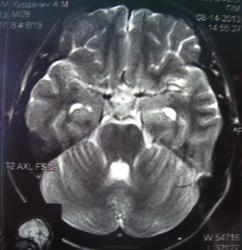

При изучении МРТ снимков головного мозга невролог указала на наличие маленьких очажков на коре головного мозга, порекомендовав обратиться за лечением к нейрохирургам. Голова также продолжает болеть, еще стали кисти рук неметь и прочие симптомы. Можете ли вы указать, имеются ли эти маленькие очажки на коре головного мозга и где именно?

Алексей, очагов достоверно не вижу, а вот на верхнечелюстную пазуху нужно обратить внимание-есть ее воспалительные изменения в виде утолщения слизистой.